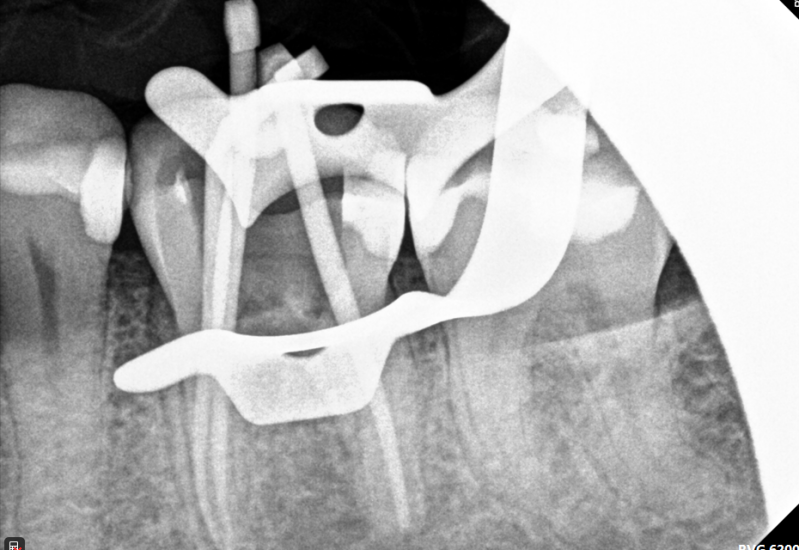

Case: RCT on Tooth #32

50-year-old female, Hyperlipidemia, Prediabetes, NKA.

Dx: Pulp necrosis and symptomatic apical periodontitis with PARL.

Tx: Non-surgical root canal therapy (RCT)

Reflection

Tooth #32 was retained due to its role as an abutment for the patient's RPD, making preservation critical. Access was complicated by mesial tilt and a metallic crown misaligned with the root axis. Treatment relieved the patient’s symptoms and maintained prosthetic function.